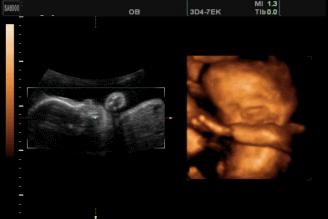

2003年,英国《卫报》报道,科学家用4D超声波成像系统拍到了26周宝宝微笑的图片。

2018年,英国《每日邮报》报道,一对夫妇在做四维彩超时发现宝宝咧嘴微笑,让父母感到喜出望外。

见诸各大网站的3D胎儿图像,也展示了胎儿在19周时微笑的模样,栩栩如生,惹人喜爱。

5个半月的胎儿大脑发育趋于完善,能够控制感觉器官,使面部具有丰富的表情。感觉器官迅速分化,味觉、听觉、触觉、视觉、听觉等都在大脑中占据了一定的空间,神经元之间的连接也开始增加了。

5个半月的胎儿相当于22周,眼睛、鼻子、眉毛、耳朵、嘴巴等五官面貌结构完整,嘴巴、眉毛活动自如,面部表情丰富也很正常。

胎儿的双顶径:5.45±0.57厘米,股骨长:3.82±0.47厘米,腹围:16.7±2.23厘米